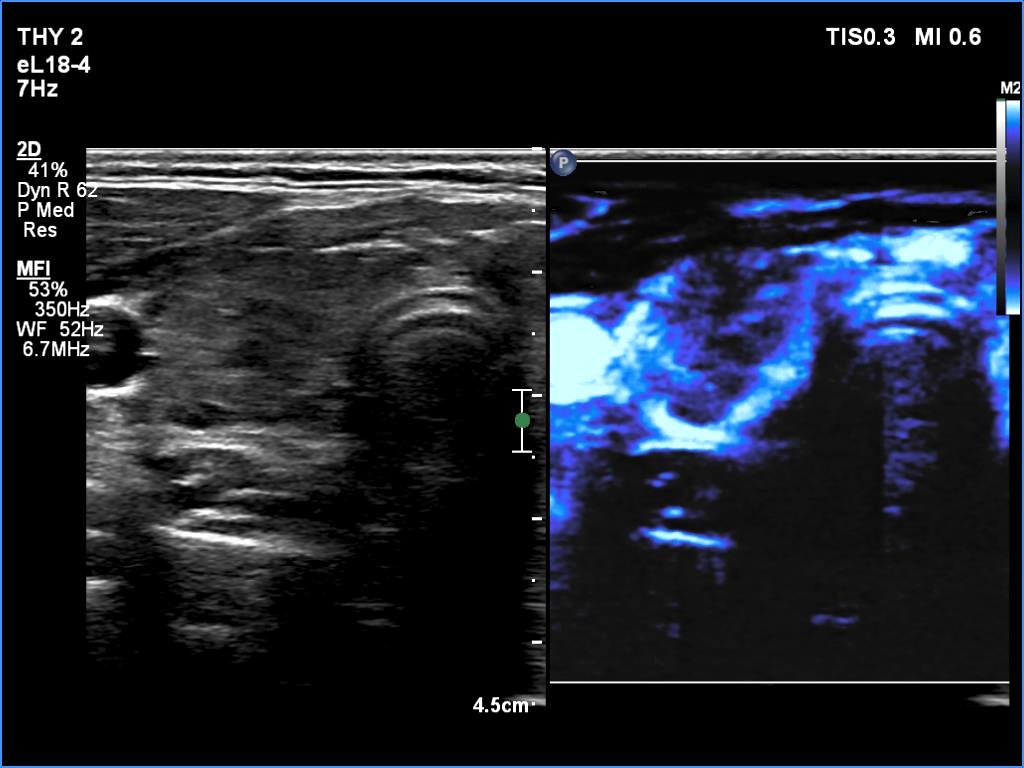

The echogenicity of the nodule - case 365 (ultrasonographic picture 4)

Five years after the first examination

Right lobe, longitudinal scan

Right lobe, transverse scan, microflow imaging.